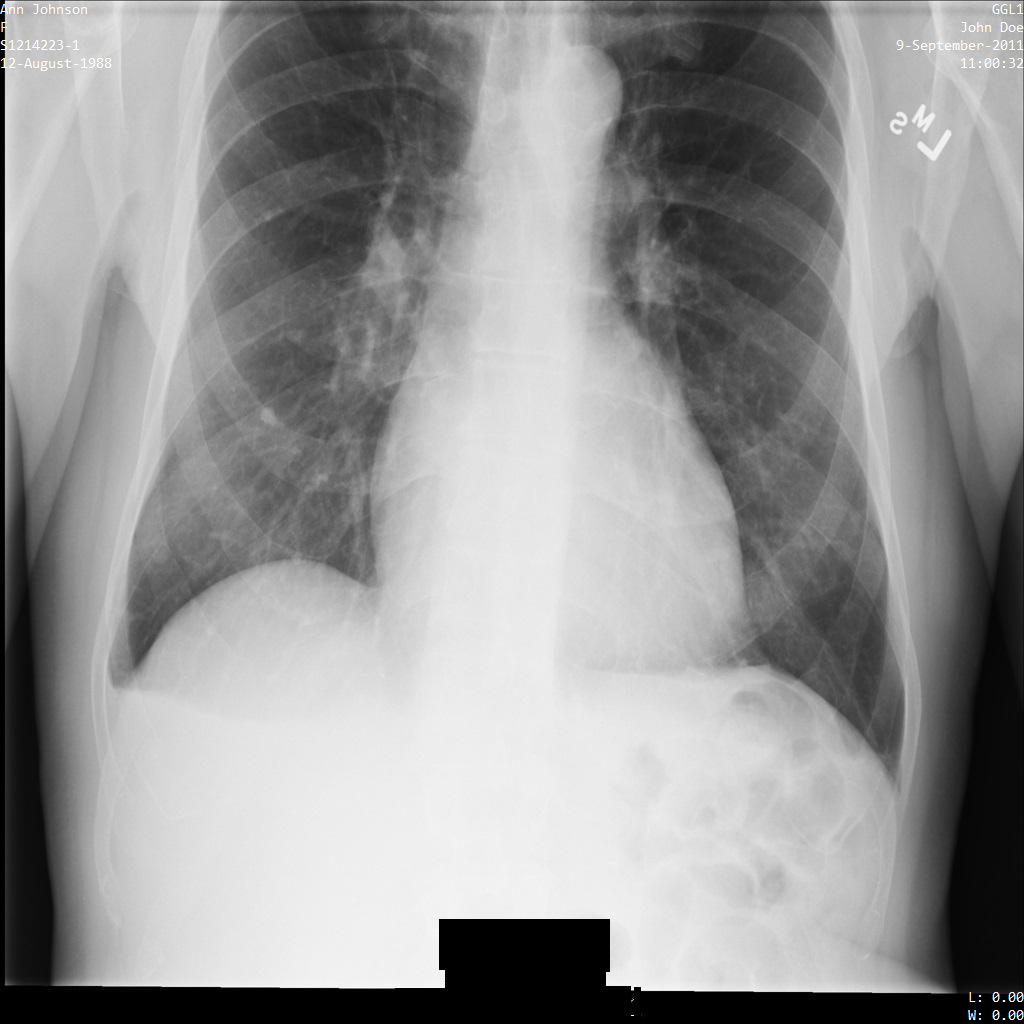

以下各部分提供的示例展示了如何使用各种方法对 DICOM 数据进行去标识化。每个示例都会提供去标识化后的图片输出。每个示例都使用以下原始图片作为其输入:

xray_original

您可以将每个去标识化操作的输出图片与该原始图片进行比较,以查看该操作的效果。